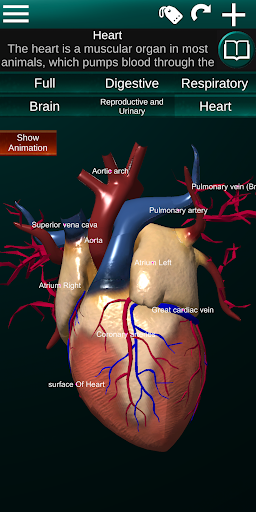

Internal Organs in 3D Anatomy لـ Vodafone Smart N9 Lite

(الأجهزة الداخلية في)

يمكنك هنا تنزيل ملف حزمة تطبيق أندرويد "Internal Organs 3D Anatomy" الخاصة بجهازVodafone Smart N9 Lite مجانًا، نسخة ملف حزمة تطبيق أندرويد - 3.4 للتحميل على Vodafone Smart N9 Lite اضغط ببساطة على هذا الزر. إنه سهل وآمن. نحن نقدم فقط ملفات حزمة تطبيق أندرويد الأصلية. إذا انتهكت أية مواد موجودة في الموقع حقوقك قم بإبلاغنا من خلال